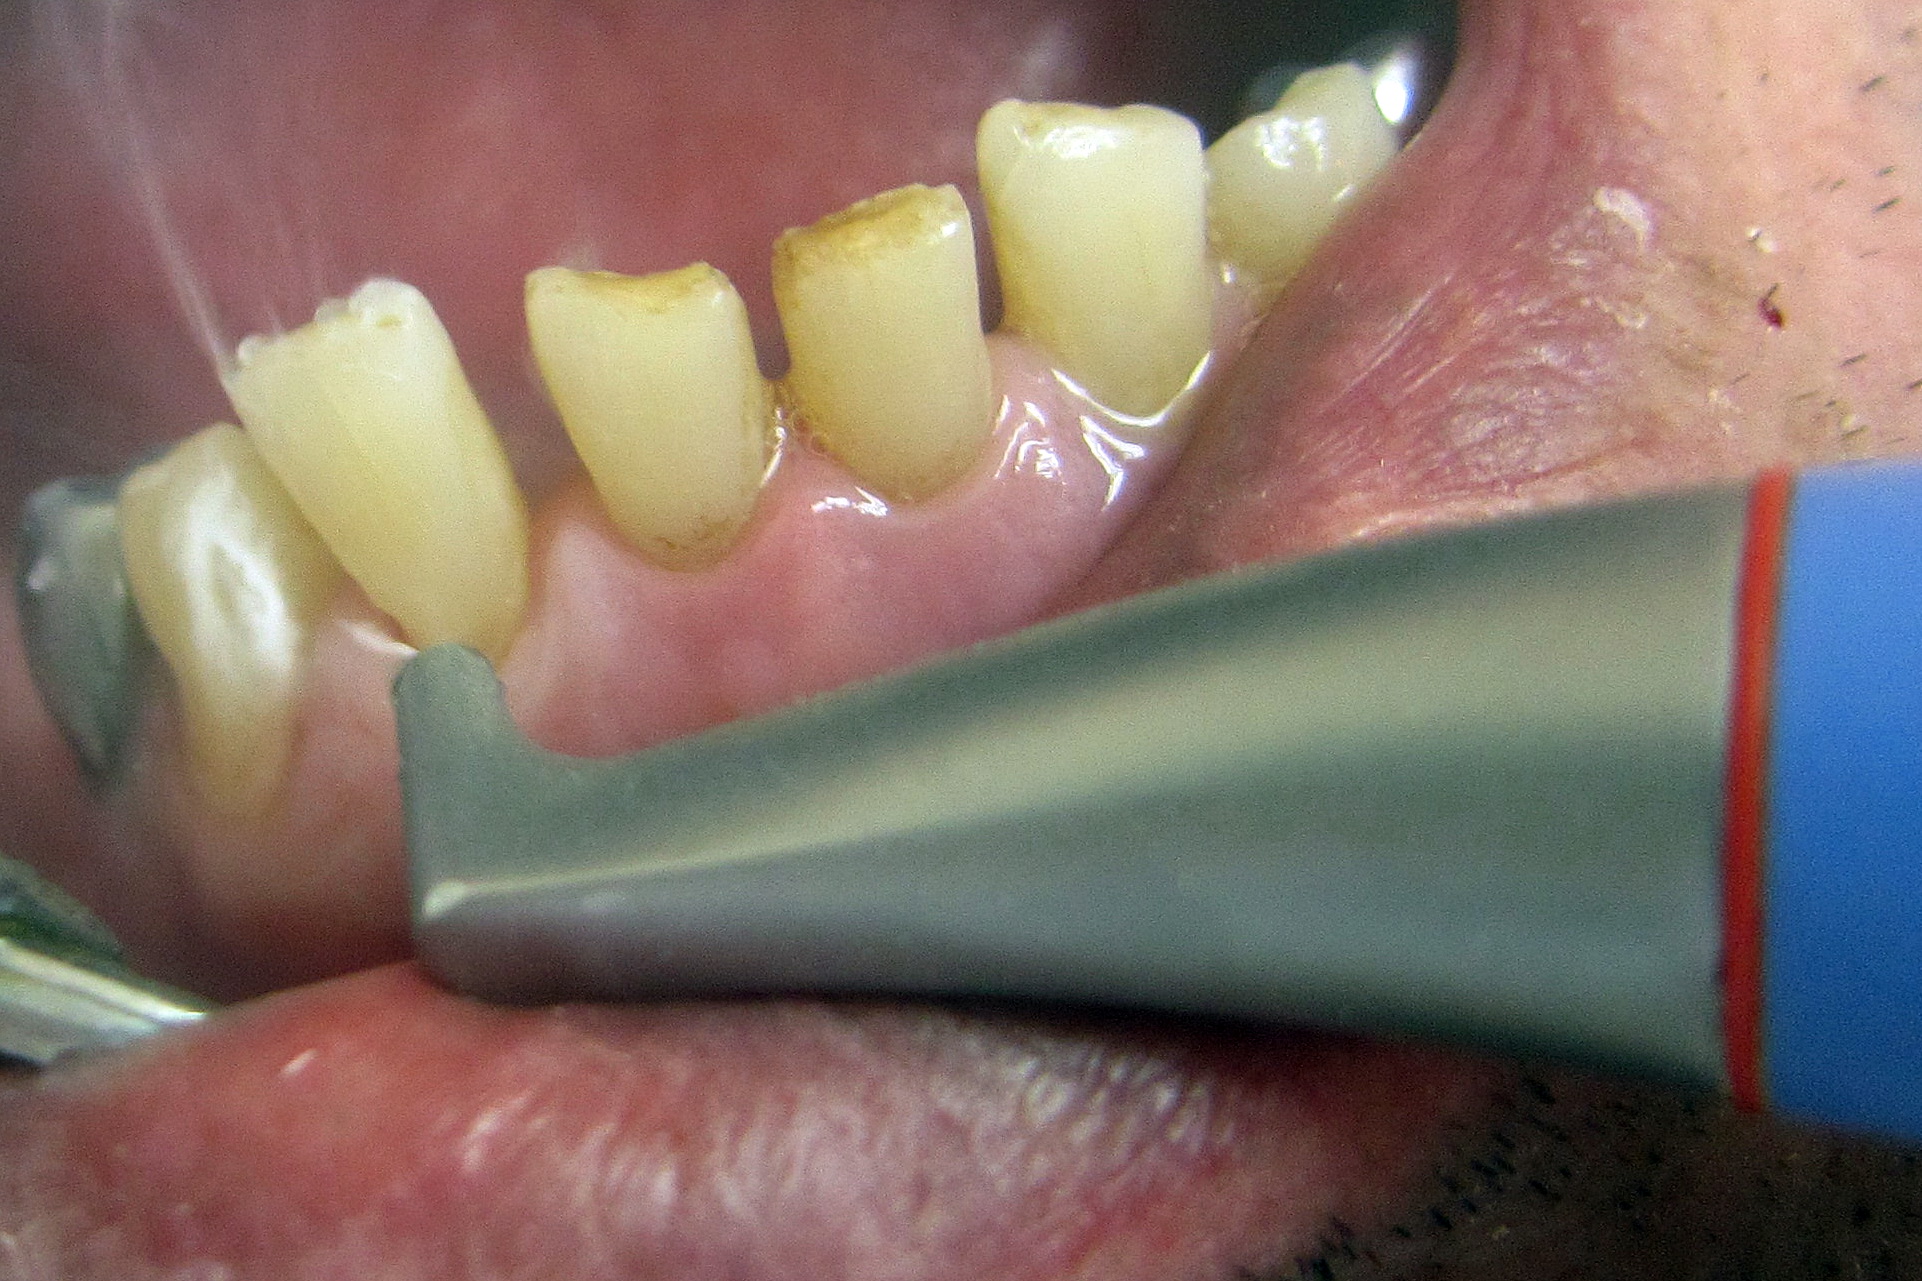

На фотографии зубы с налетом и отложениями из-за неправильной гигиены полости рта.

Перед началом лечения кариеса необходимо очистить ротовую полость от зубных отложений. То есть осуществить профессиональную чистку зубного ряда.